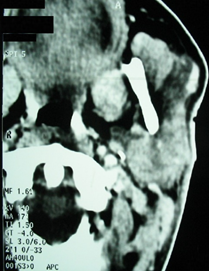

Parotid ultrasound showed an enlarged parotid with a heterogeneous tumor, poorly defined, and hyper vascularized on Doppler, associated with multiple satellite adenopathies (Figure 1). Computed tomography (CT) scan showed a parotid swollen by a parenchymal tumor, hypodense, heterogeneous, and enhancing heterogeneously after injection of contrast product. This tumor infiltrated the peri-parotid fat with multiple adenopathies of secondary appearance (Figure 2 & 3).

Figure 1 Cervical ultrasound: Heterogeneous tumor of the left parotid gland (A) with multiple enlarged lymphatic nodes (B).